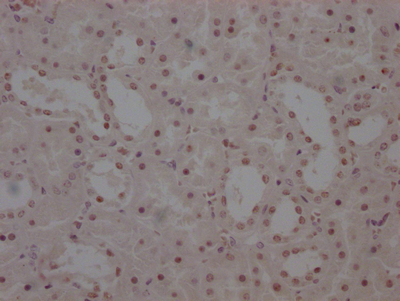

The image on the left is immunohistochemistry of paraffin-embedded Human thyroid cancer tissue using CSB-PA985822(ATP2A3 Antibody) at dilution 1/30, on the right is treated with synthetic peptide. (Original magnification: ×200)

The image on the left is immunohistochemistry of paraffin-embedded Human liver cancer tissue using CSB-PA985822(ATP2A3 Antibody) at dilution 1/30, on the right is treated with synthetic peptide. (Original magnification: ×200)